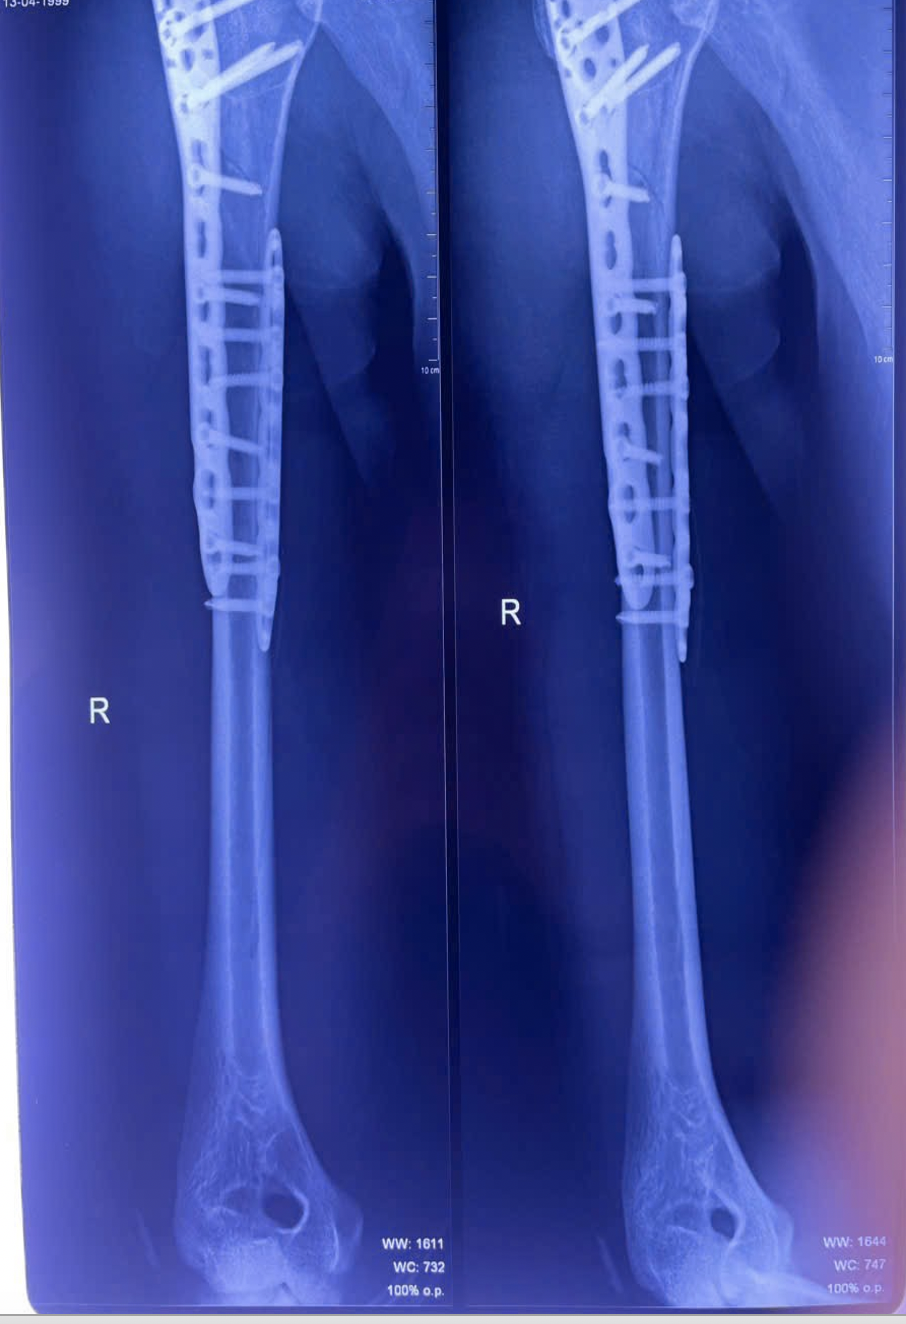

Kết quả chụp X-quang ngực tại giường cho thấy nam thanh niên bị tràn khí màng phổi phải do chấn thương dập phổi nặng, kèm gãy phức tạp đầu trên và gãy chéo dài 1/3 trên xương cánh tay phải”, BS.CKI Sơn Tấn Ngọc, khoa Chấn thương chỉnh hình cho biết.

Xương cánh tay phải của người bệnh bị gãy hoàn toàn, kèm dấu hiệu tràn khí màng phổi (Ảnh: BVCC).

Sau phẫu thuật, vị trí gãy xương cánh tay được cố định vững chắc. (Ảnh: BVCC)

Suốt gần 3 giờ, ê-kíp khoa Chấn thương chỉnh hình đã thực hiện thành công ca phẫu thuật. Ổ gãy được xử lý triệt để, rửa sạch, loại bỏ máu tụ, nắn chỉnh và cố định bằng nẹp titan cùng vít khóa.

Dưới sự hỗ trợ của hệ thống C-arm hiện đại, cấu trúc xương tại vị trí tổn thương của bệnh nhân được cố định vững chắc và các đầu vít không ảnh hưởng đến mặt khớp.